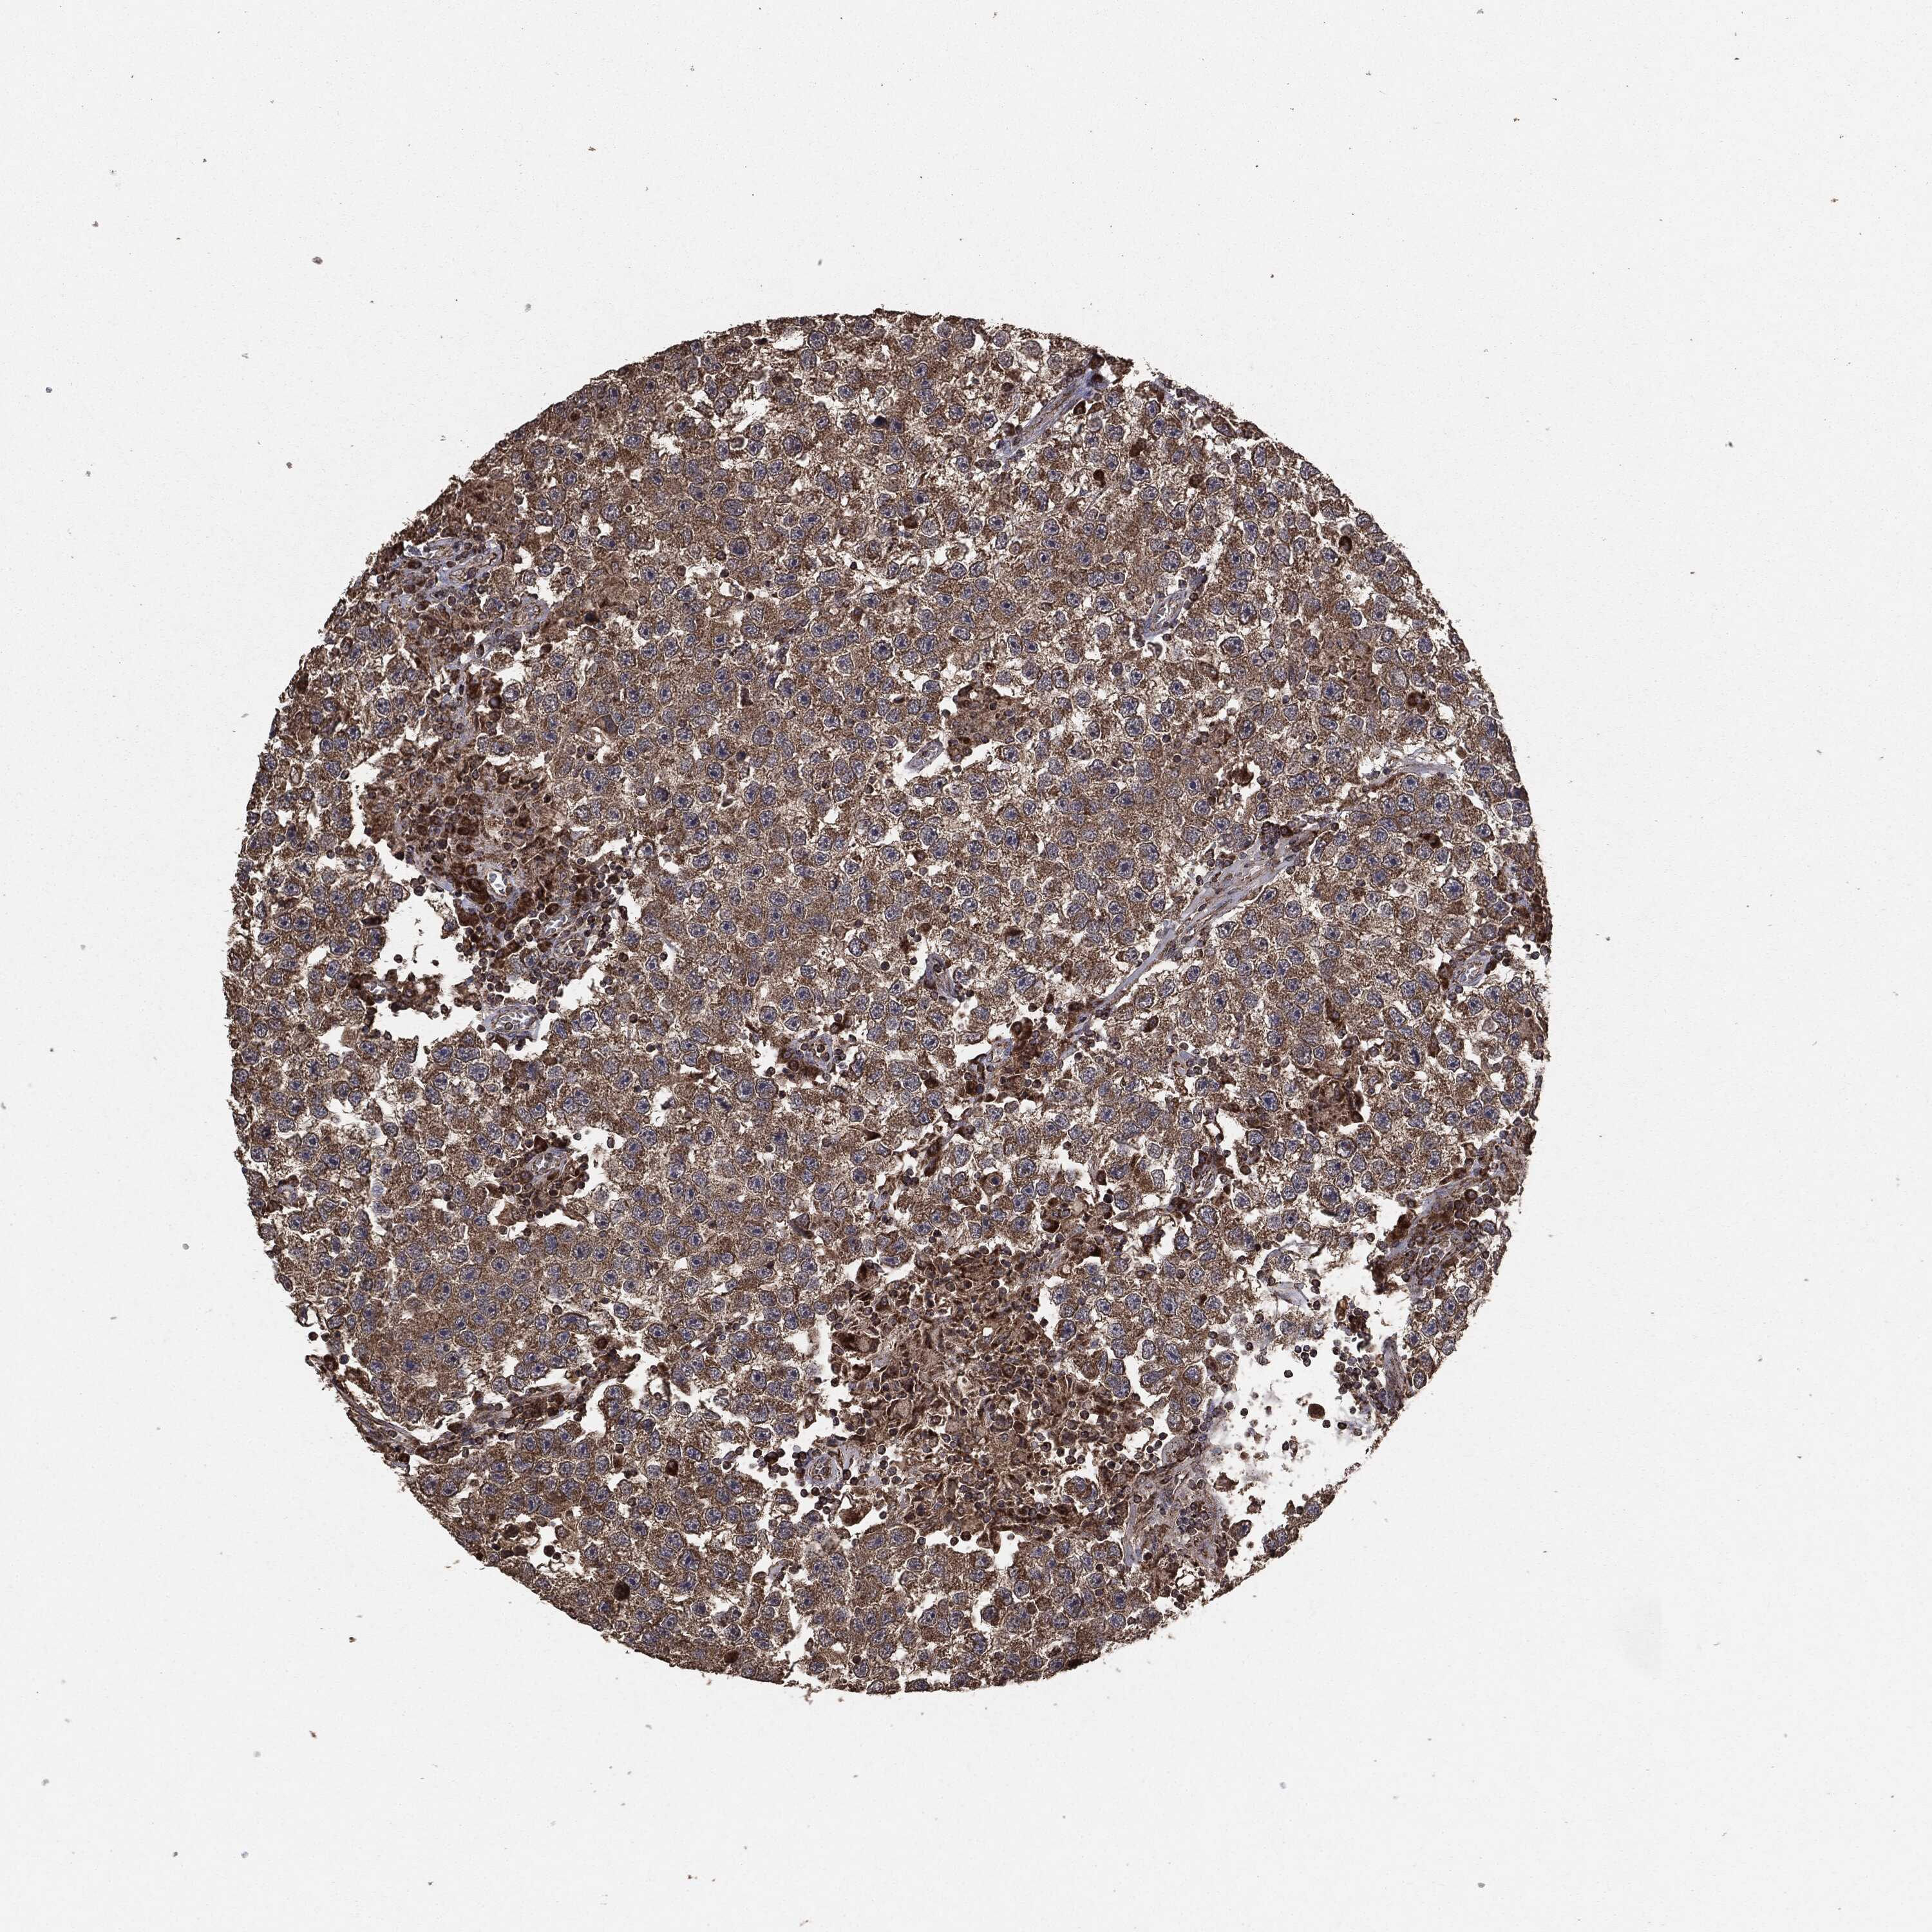

TESTIS CANCER - Protein expressioni

A mouse-over function shows sample information and annotation data. Click on an image to view it in a full screen mode. Samples can be filtered based on level of antibody staining by selecting one or several of the following categories: high, medium, low and not detected. The assay and annotation is described here.

Note that samples used for immunohistochemistry by the Human Protein Atlas do not correspond to samples in the TCGA dataset.

Antibody stainingi

Antibody staining in the annotated cell types in the current human tissue is reported as not detected, low, medium, or high, based on conventional immunohistochemistry profiling in selected tissues. This score is based on the combination of the staining intensity and fraction of stained cells.

Each image is clickable and will lead to virtual microscopy that enables deeper exploration of all samples and also displays staining intensity scores, fraction scores and subcellular localization as well as patient and tissue information for each sample.

Seminoma, NOS

Carcinoma, Embryonal, NOS

Teratoma, malignant, NOS

Urothelial carcinoma, High grade